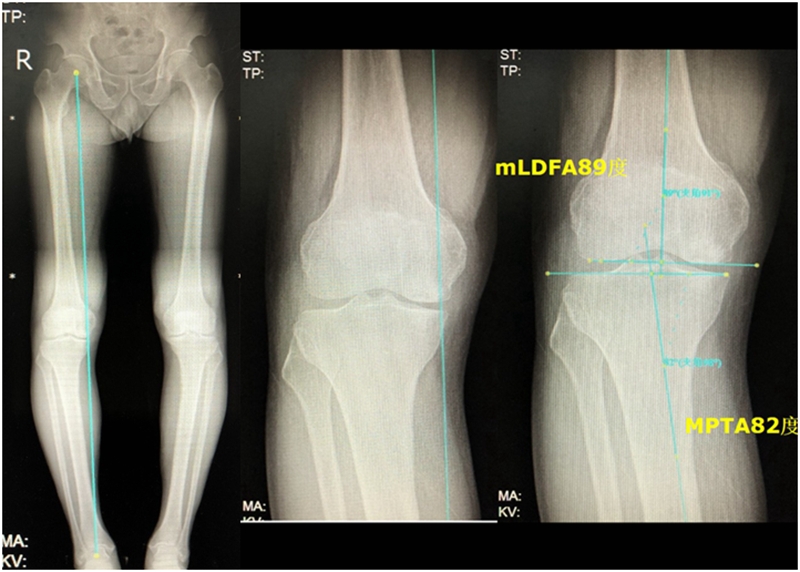

关于SONK与下肢力线的关系,一项研究结果显示SONK组MPTA畸形比OA组更大,高达约1.5°,SONK组JLCA也显著高于OA组。

提示胫骨近端内翻畸形和膝关节松弛,有助于诱发SONK,SONK骨软骨病变的大小受胫骨近端内翻畸形的影响。临床中MPTA小于 84°且伴有急性膝关节疼痛应尽快MRI检查。

国内一项研究纳入内侧半月板损伤患者97例,男40例,女57例,年龄32~66岁,通过MRI测量半月板外突>3mm者38例,无半月板外突者59例。膝内翻患者半月板突出的发生率为89%,半月板根部撕裂患者半月板突出的发生率为78%,证明膝内翻、内侧半月板根部撕裂是造成内侧半月板突出的主要危险因素。

膝内翻 内侧半月板根部撕裂

病例2:女,69岁,主诉左膝关节内侧疼痛1月余。2017年11月X光见右膝股骨髁负重区的软骨下区域出现了椭圆形透亮影,MR检查见股骨内侧髁骨坏死,合并内侧半月板外突和后角层裂,半月板相对突出百分比(RPE)25.32%,矢状位病变区域前后径为23.96mm,关节线会聚角6°。

病例1:男,64岁,主诉左膝关节内侧疼痛6年余。MR提示骨坏死区占比为33.28%,矢状位病变区域前后径为26.42mm,半月板相对突出百分比(RPE)31.78%,同时存在胫骨侧来源的下肢内翻畸形(MPTA83°),关节线会聚角2°。

行关节镜检查+软骨摘除+微骨折+HTO术,术后随访2年恢复良好,活动自如,行走时无左膝关节疼痛不适。